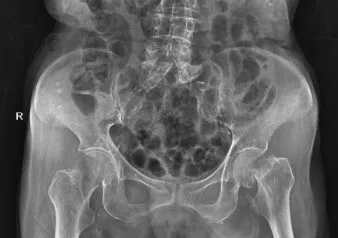

不久前,97岁高龄的曾奶奶在小区里不慎跌倒,导致左髋部位出现肿痛,且活动功能严重受限,随后被紧急送至我院就诊。经过详细检查,曾奶奶被确诊为左股骨颈基底部骨折;此外,曾奶奶还有合并有高血压病等多种慢性病,这无疑为治疗增添了难度。

▲术前DR显示:左股骨颈骨折